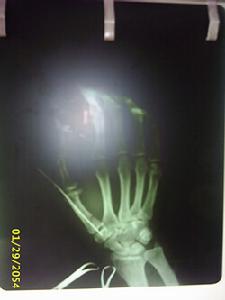

第一掌骨基底骨折經皮克氏針內固定

第一掌骨基底骨折經皮克氏針內固定多由直接暴力如打擊或擠壓傷所造成,可以為單一或多個掌骨骨折。骨折類型以橫斷和粉碎者多見,因扭轉和間接暴力亦可發生斜形或螺旋形骨折。治療上既要充分固定又要...

疾病簡介 治療原則 第一掌骨骨折 其他掌骨骨折 掌骨幹骨折第1掌骨基底部骨折脫位又稱Bennett骨折脫位,是一種極不穩定的骨折。拇指腕掌關節是由第1掌骨與大多角骨構成的鞍狀關節,靈活而穩定。當第1掌骨處於輕度...

發病原因 發病機制 臨床表現 檢查 治療固定。內固定方法1.克氏針內固定 適用於近、中節指骨初掌骨橫斷骨折。克氏針...,以切開逆行交叉針固定為宜。切開逆行交叉克氏針內固定技術的注意事項:①指骨骨折...感染。對於多發掌骨骨折作克氏針內固定時,還要考慮到掌橫弓的排列。每一掌骨...